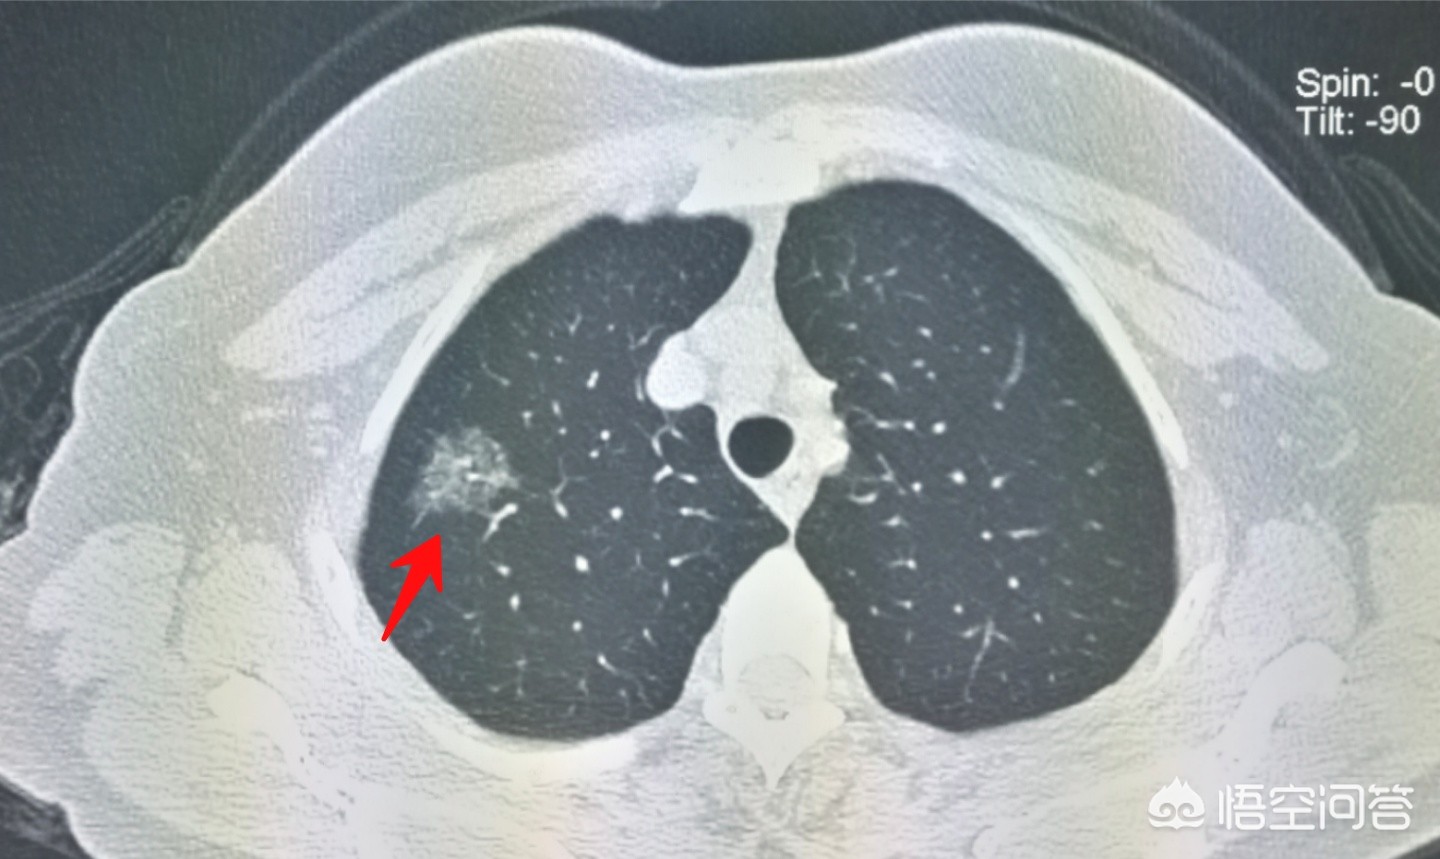

上图这位女士才30多岁,因为她小姨查出肺癌正在治疗中,心里紧张,也过来做了体检,结果发现微浸润腺癌。

如果不是这次体检,很可能在几年后进展成晚期癌症。

像这位女士,体检发现9毫米磨玻璃结节,随访观察结节密度增高,手术切除治愈,病理是原位癌。